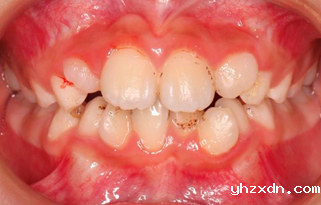

A 9 years old child, with 3-year treatment, two-phase combined treatment. Chief complaint: crowding, insufficient space, and desire to avoid extractions in the future